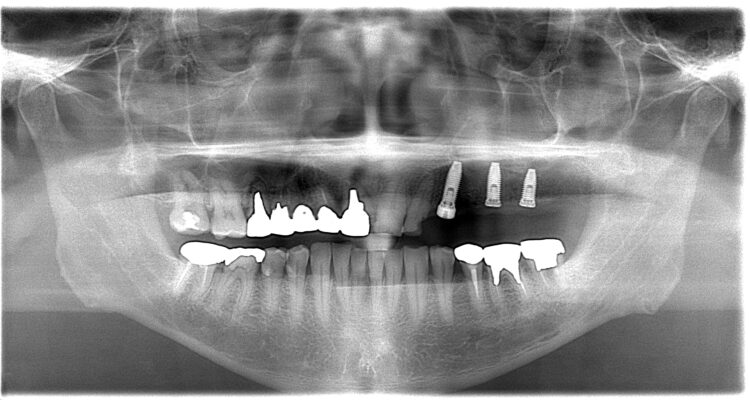

<Before >

写真では上顎洞に骨が足されているのがわかります。

骨をしっかり足すことでインプラントを埋入することができました。